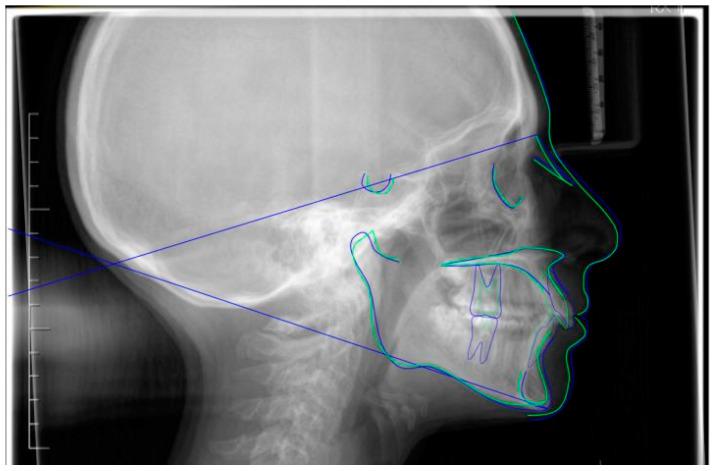

Successful closure of edentulous spaces with clear aligners (CAs) is influenced by many factors. CAs are tailored orthodontic devices whose predictability may have relevant medico-legal implications. This study presents a scoping review about missing molar space closure (MMSC) with CAs and a clinical case. This study aims to highlight the feasibility of molar space closure by mesialization with CAs without hybrid supports. Following PRISMA Sc-review guidelines, English-written randomized/non-randomized/observational clinical studies on PubMed, Scopus, Cochrane and Lilacs were searched. An 18-year-old patient, with upper and lower edentulous spaces due to the loss of two first molars, was rehabilitated with CAs (Sorridi, Sorridi srl, Latina, Italy) without hybrid supports and attachments. The therapy was carried out over 10 months. Currently, there are no studies documenting MMSC by mesialization with only CAs. Existing articles document the closure of premolar or incisor spaces. The upper and lower left second molars replaced the missing first molars, and erupting third molars replaced adjacent teeth. The biomechanical effects in space closure with CAs related to extraction cases appear as priorities of clinical/medico-legal interest. Our case turns attention to this movement of CAs without attachments/hybrid supports, indicating that even such a complex treatment can be comfortable for patients and safely predictable for specialists.

使用透明矫治器(CA)成功关闭无牙间隙受多种因素影响。CA是定制的正畸装置,其可预测性可能具有相关的医疗法律意义。本研究呈现了一项关于使用CA关闭缺失磨牙间隙(MMSC)的范围综述及一个临床病例。本研究旨在强调在无混合支持的情况下通过CA近中移动关闭磨牙间隙的可行性。遵循PRISMA范围综述指南,检索了PubMed、Scopus、Cochrane和Lilacs上英文撰写的随机/非随机/观察性临床研究。一名18岁患者因两颗第一磨牙缺失导致上下无牙间隙,使用CA(Sorridi,Sorridi srl,拉蒂纳,意大利)进行修复,无混合支持和附件。治疗持续了10个月。目前,尚无研究记录仅通过CA近中移动关闭MMSC的情况。现有文章记录了前磨牙或切牙间隙的关闭。上下颌左侧第二磨牙替代了缺失的第一磨牙,萌出的第三磨牙替代了相邻牙齿。与拔牙病例相关的CA关闭间隙的生物力学效应似乎是临床/医疗法律关注的重点。我们的病例将注意力转向了无附件/混合支持的CA这种移动方式,表明即使是如此复杂的治疗对患者来说也可以是舒适的,对专家来说也可以是安全可预测的。